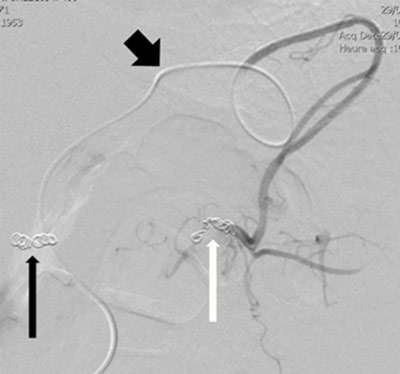

Figure 4b

Microcoils embolization of the distal splenic artery (white arrow) through superselective catheterism of the gastroepiploic arteries (thick black arrow); the thin black arrow indicates the previous ostial coiling.

Six days later, the patient presented a slow decrease of his blood hemoglobin (7.4 g/dl). A new contrast-enhanced CT scan revealed a new retrogastric blood extravasation originating from the distal third of the splenic artery (Figure 4a). A superselective catheterization of the gastroepiploic arteries by a 3F microcatheter allowed coil embolization of the distal splenic artery (“sandwich” method in two stages, see infra), hence stopping the bleeding (Figure 4b). After three months of chemotherapy, there was a reduction of the size of the pancreatic adenocarcinoma but also occurrence of liver and bone metastases. The patient died eight months later.